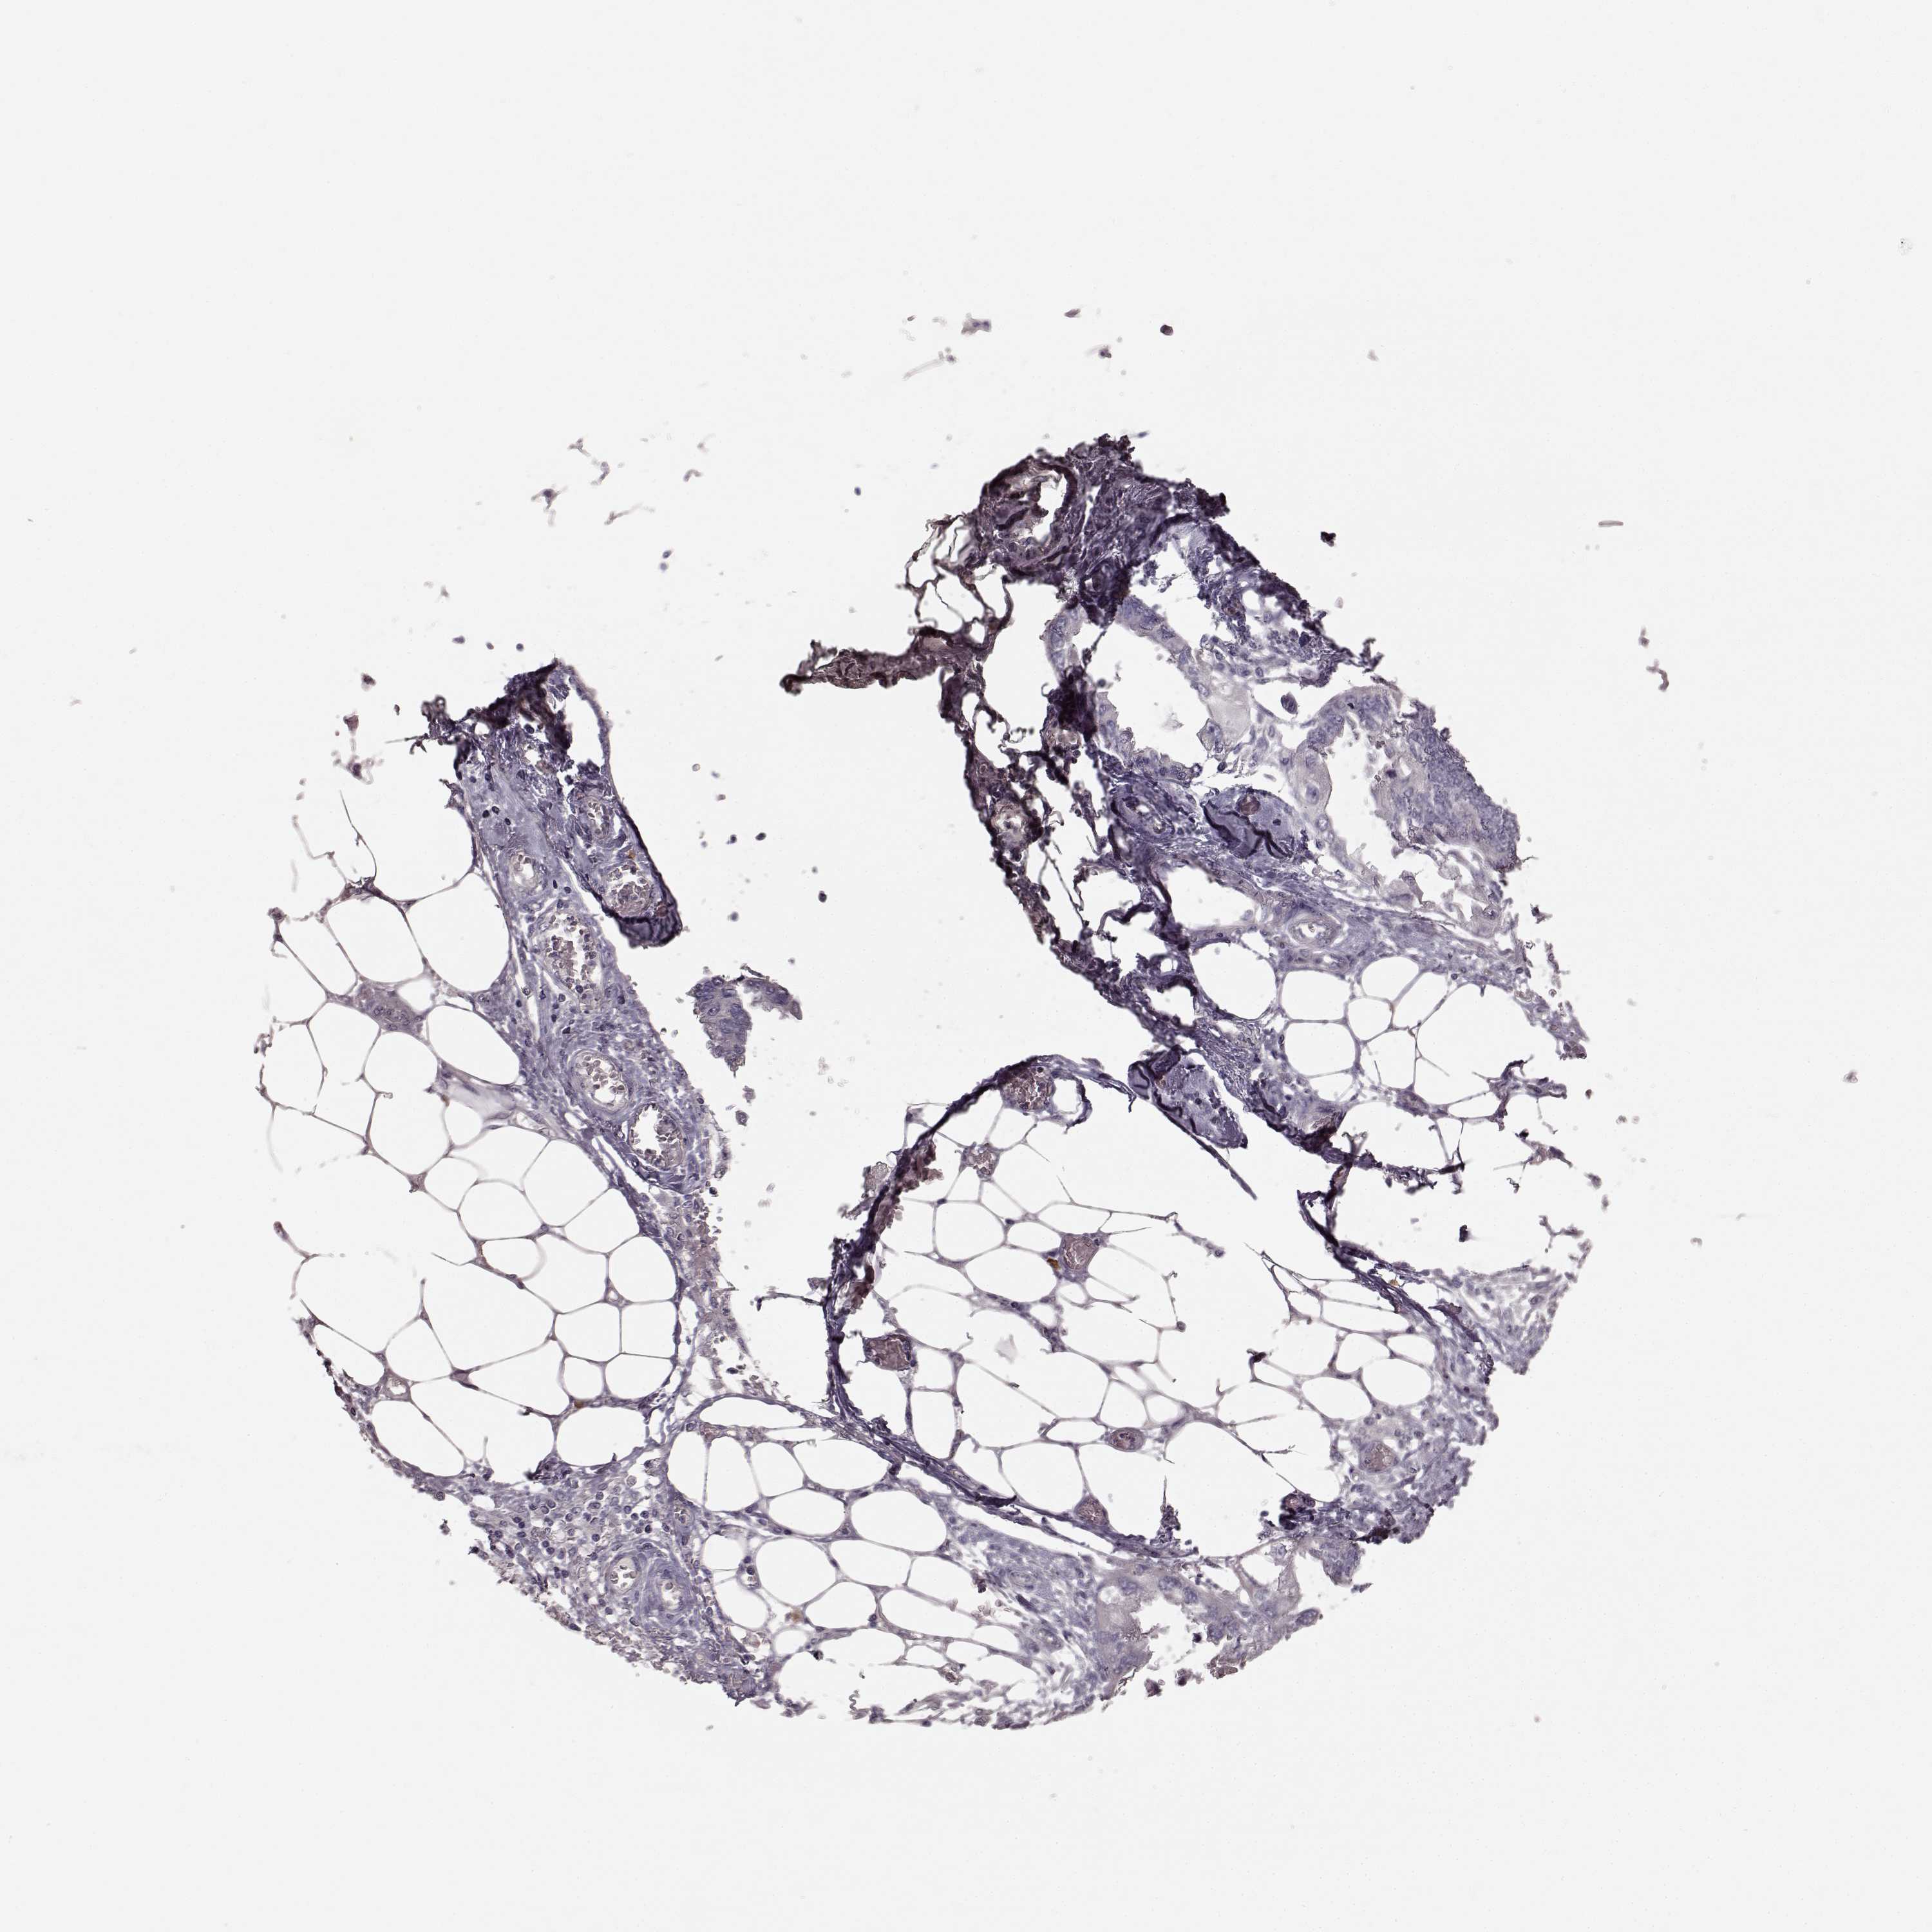

ENDOMETRIAL CANCER - Protein expressioni

A mouse-over function shows sample information and annotation data. Click on an image to view it in a full screen mode. Samples can be filtered based on level of antibody staining by selecting one or several of the following categories: high, medium, low and not detected. The assay and annotation is described here.

Note that samples used for immunohistochemistry by the Human Protein Atlas do not correspond to samples in the TCGA dataset.

Antibody stainingi

Antibody staining in the annotated cell types in the current human tissue is reported as not detected, low, medium, or high, based on conventional immunohistochemistry profiling in selected tissues. This score is based on the combination of the staining intensity and fraction of stained cells.

Each image is clickable and will lead to virtual microscopy that enables deeper exploration of all samples and also displays staining intensity scores, fraction scores and subcellular localization as well as patient and tissue information for each sample.

Antibody HPA067812

Antibody HPA071461

Staining

High

Medium

Low

Not detected

Intensity

Strong

Moderate

Weak

Negative

Quantity

>75%

75%-25%

<25%

None

Location

Nuclear

Cytoplasmic/membranous

Cytoplasmic/membranous,nuclear

Adenocarcinoma, metastatic, NOS